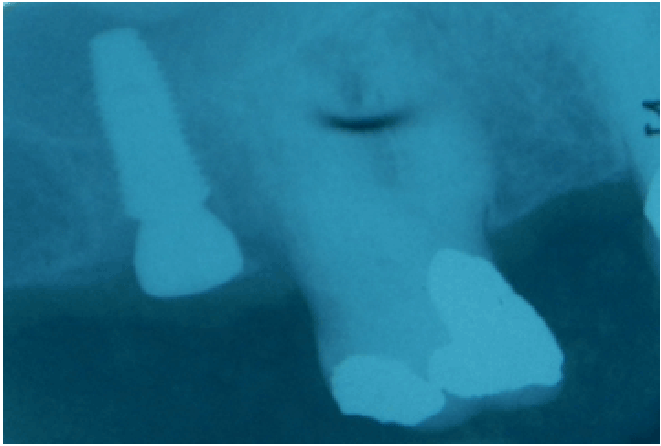

图12:在常驻基台和临时皇冠发出后采取的恐慌射线照片。我们可以在直接装载的植入物(左图)周围观察稳定的嵴骨水平。